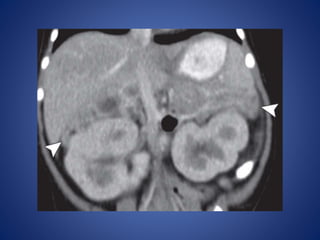

At CT, large ACNs show heterogeneous, predominantly peripheral

enhancement.

The tumor may be surrounded by a thick, capsule-like rim that

enhances. Fine or coarse calcification is seen at CT in about 30% of

cases